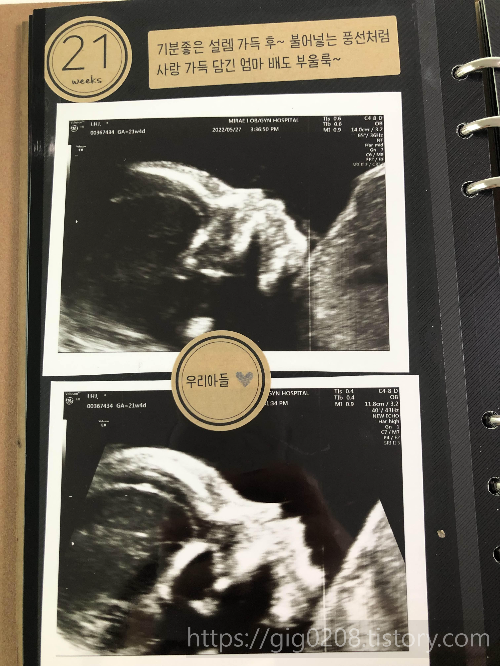

2022.5.27(금)_ 임신 21주+4일_정밀초음파검사

정밀초음파라해서 아기 얼굴나오는 컬러 입체초음파하는줄 알고

엄청 설레면서 검사하러갔다.

근데 그게 아니었고, 태아의 발육상태를 꼼꼼히 보는 엄청 중요한 초음파였다.

| *20주~21주 정밀초음파 -정밀초음파를 통해 태아 기형의 실제 유무와 기형의 정도, 발육상태 등 정확한 태아상태를 정밀초음파를 통해 확인가능 내부 장기의 이상소견 즉 뇌, 장기, 골격 등 많은 항목을 단 시간 내에 집중적으로 검사 |

하랑이 콧구멍 2개, 손가락 5개, 발가락 5개, 귀 2개등 확인하는데

신기하면서 너무 설렜다.

심장이 잘뛰는지, 혈액이 잘 흘러가는지 설명해주셨지만

은근 걱정되기도했다. 혹시나 먼가 잘못된게 발견되는건 아닌지ㅠㅠㅠㅠ

초음파사진보면서 너무 신기해서 계속 보게됬다.

이제 사람이구나라는 느낌을 받게되는거 같다.

산부인과 선생님이 정밀초음파한걸 보시더니, 다 정상이라고 하셨다.

그러면서 진료하면서 다시 초음파를 했는데, 하랑이가 손가락을 빨고있었다.

선생님이 진료 지금까지하면서 손가락빠는 건 처음본다고 하셨다.

우리 하랑이 천잰가???????????

정밀초음파도 대성공~!!